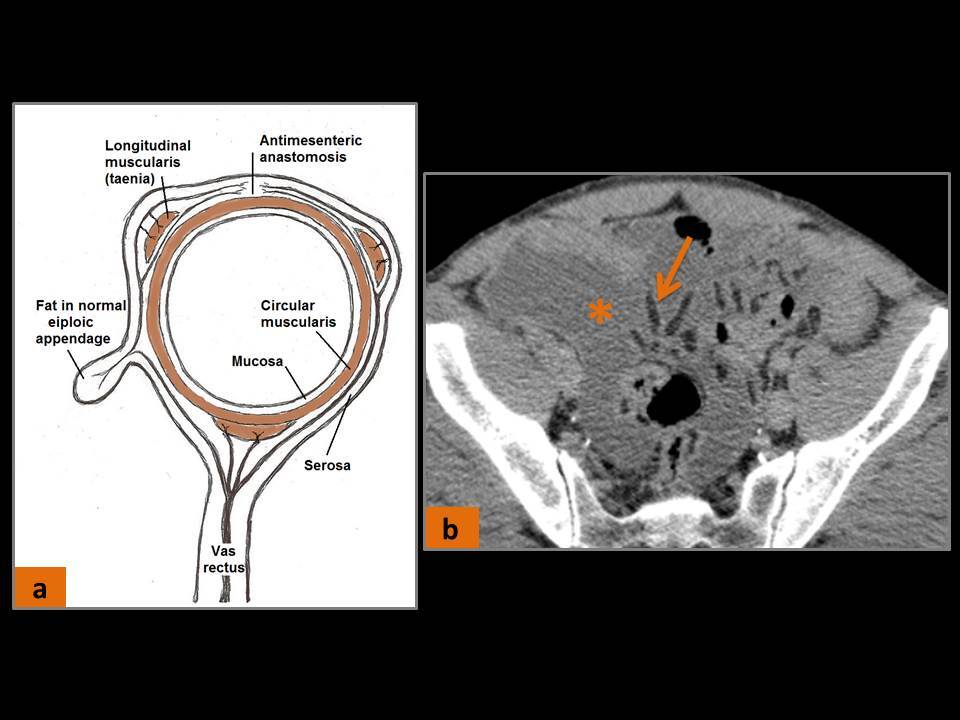

Apêndice epiploico?

Projeções de gordura subserosa revestidas por peritônio que localizam-se na superfície do cólon. Duas fileiras: Medial (taenia libera); Póstero-lateral (taenia omentalis).

Normalmente invisíveis nos exames. Podem ser visualizadas se rodeadas por contraste, ascite ou hemoperitônio

Suprimento sanguíneo do apêndice epiploico?

1 a 2 pequenas artérias perfurantes vindas da serosa colônica. Essas perfurações são também locais propensos a surgimento de divertículos.

(Torção com oclusão venosa ou arterial levam à apendagite)

(seta) – apêndices epiploicas normais delineadas por ascite (*).